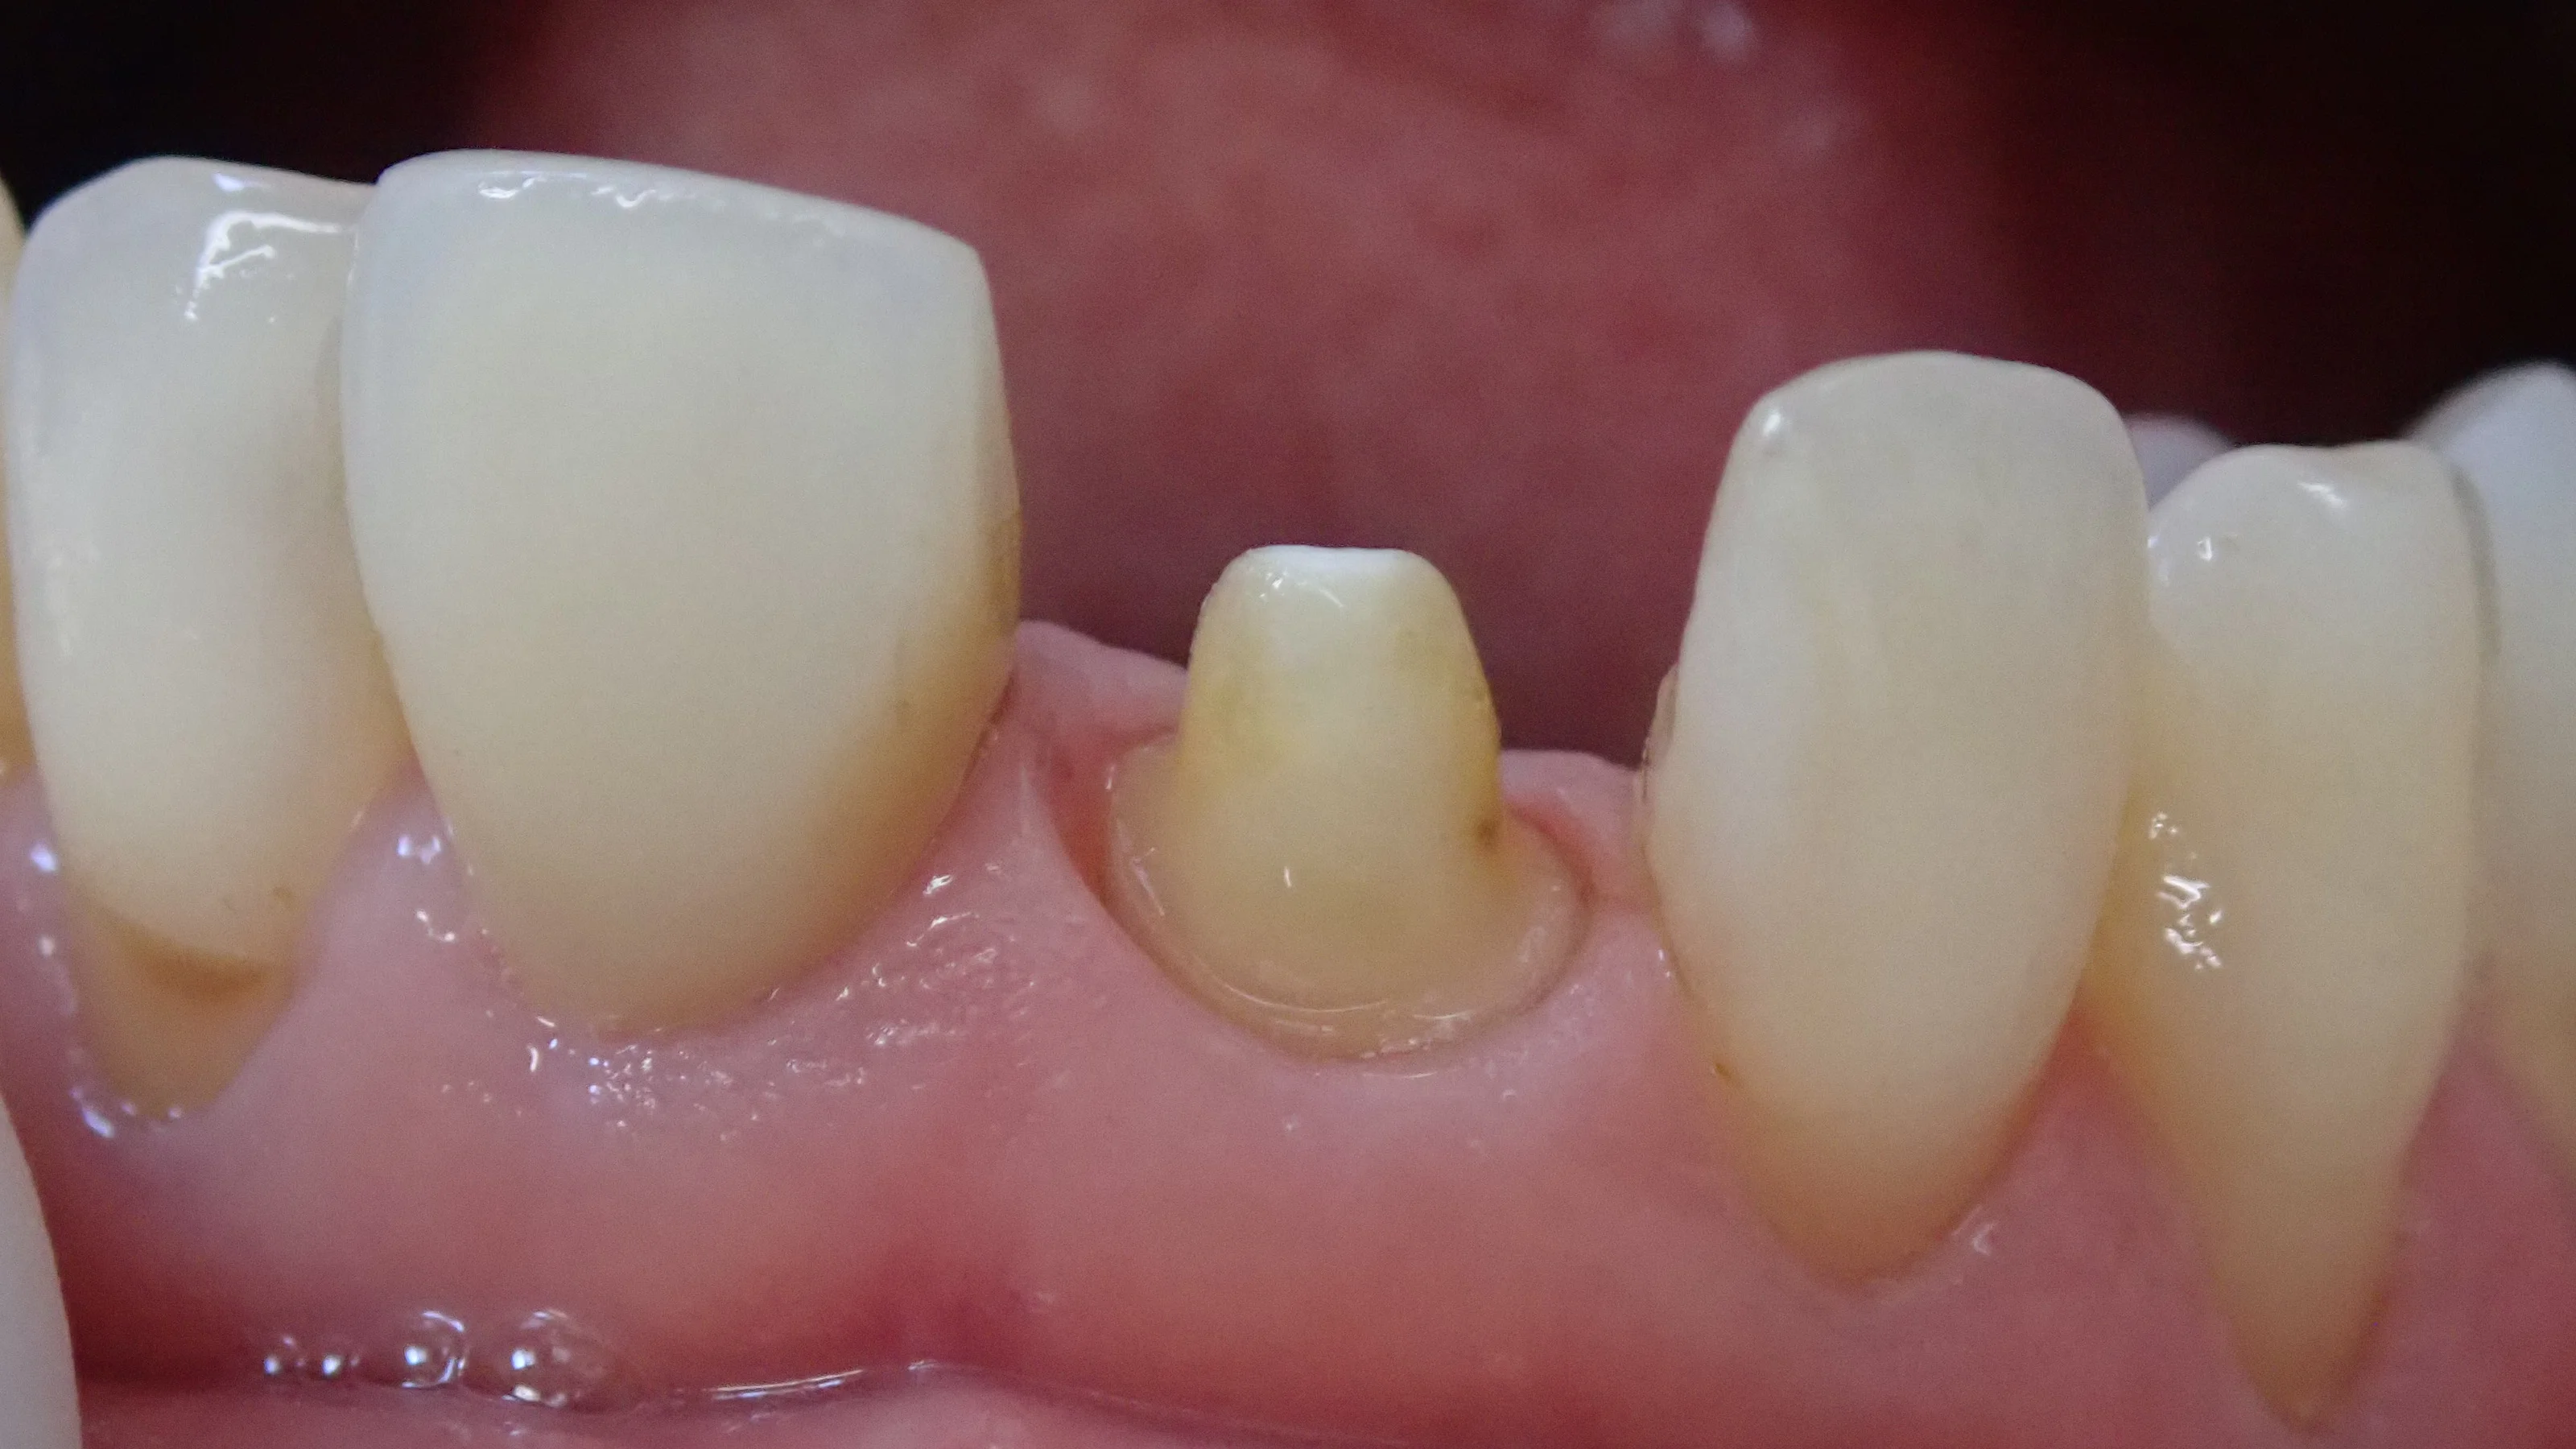

では、まずは仮歯の時の写真です。

で、仮歯を外して・・・仮のセメントを除去したのがこちらです。